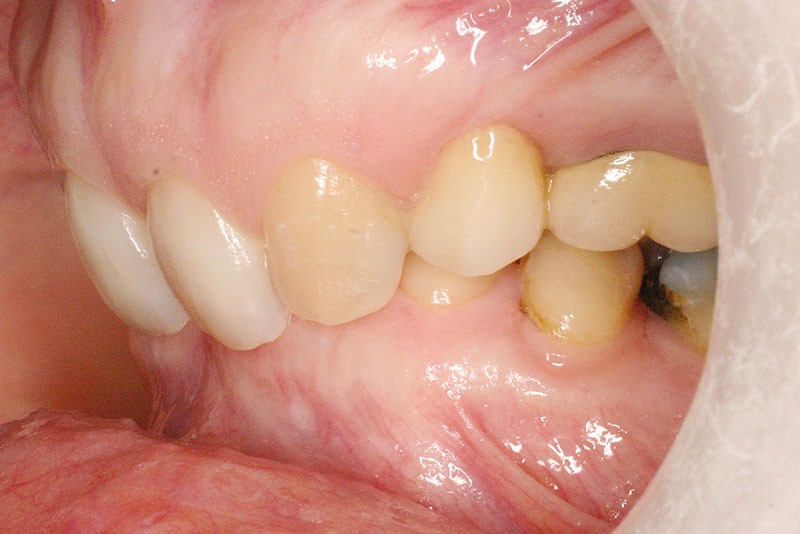

La patiente, âgée de 30 ans, présente des agénésies multiples : 12, 22, 14, 15, 24, 25, 35 et 45 (fig. 1 à 3).

Malocclusion de classe II par rétrognathie mandibulaire dans un schéma squelettique hypodivergent (fig. 4 à 6).

On note une forte supraclusion incisive (fig. 7 à 9).

Un traitement orthodontique a déjà été effectué pendant son adolescence avec un choix de fermeture d’espaces qui a entraîné une linguoversion incisive maxillaire excessive (fig. 10), avec un préjudice esthétique important notamment sur le sourire (fig. 11 à 13).